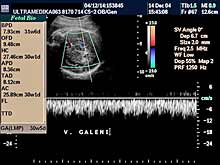

C) III trimestar trudnoće

od 24. do 40. nedelje trudnoće

Indikacija za ultrazvučni pregled:

- Procena funkcije bubrega, organa abdomena, srca i cirkulacije likvora

u mozgu.

Napomena: Na svakom pregledu do kraja trudnoće.

- Procena relativnih i organskih suženja sabirnog sistema bubrega i

izvodnih kanala bubrega i mokraćne bešike.

Napomena: Obavezna primena

3D Sono CT i XRes.

- Procena eventualnih suženja izvodnih traktova srca ploda.

Napomena:

Primena Broadband - CD ili CPA i 3D CPA.

- Stalna procena ehostrukture organa ploda i njegov ukupni porast.

Napomena: Kod "hiperehogenih bubrega" procena renalnih aretrija CPD.

Stalna procena volumena pluća, želudca i veličine creva.

- Procena bolesti histiogeneze mozga ploda od 26 nedelje gestacije.

Napomena: Procena moždane cirkulacije Broadband - CD i CPA i/ili 3DCPA.

- Procena izostanka treće faze embriogeneze mozga

OD 26 NEDELJE DO KRAJA

TRUDNOĆE.

- Registrovanje destruktivnih lezija mozga fetusa.

Napomena: Mogu

nastati krvarenja mozga zbog nedostatka vitamina K (hemoragija

intrakranijalis - HIC), hipoksično-ishemične promene koje dovode do

periventrikularne i subkortikalne leukomalacije - PVL i SCL.

- Registrovanje pojave tumora organa ploda i otkrivanje infekcija ploda.

Napomena: Mada su tumori ploda retki, obično se registruju u drugoj

polovini trudnoće. Njihova tačna i blagovremena dijagnoza je u većini

slučajeva ključna u lečenju deteta.

- Od 28. nedelje procena spuštenosti testisa.

Napomena: Ova informacija

je ključna za lečenje u slučaju izostanka dospevanja testisa u skrotume u toku trudnoće.

- Procena funkcije žučnih i pankreasnih puteva.

Napomena: Blagovremena

dijagnoza omogućava i hitnu odluku o hirurškom lečenju bebe,

neposredno nakon rođenja.

- Od 34. nedelje gestacije procena epifiza kolenih zglobova. Napomena:

Ključna informacija u slučaju postojanja bolesti štitne žlezde ploda

koja je praćena zastojem razvoja inteligencije nakon rađanja bebe.

- U slučaju zastoja porasta ploda procena redistribucije krvotoka i

određivanja termina porođaja.

Napomena: Tačnost je zasnovana na

primeni Broadband Color Dopplera i Color Power Dopplera.

- Procena posteljice i protoka pupčanika, kao i njegov tok i položaj.

Napomena: mogućnost pogrešnog položaja pupčanika na posteljici,

njegovo prednjačenje u porođaju, ili njegov neadekvatan položaj oko

dela tela ploda, ili formiranje čvora ili zapušenje, su krucijalna

informacija u toku pregleda do tada normalne trudnoće.

- U 37. nedelji trudnoće procena veličine grlića endovaginalnom sondom.

Napomena: Dužina i izgled grlića mogu pouzdano odrediti termin carskog

reza i očekivanog porođaja, i mogućnosti ili ne mogućnost završetka

porođaja indukcijom.

|

U III trimestru pregled trudnoće zbog velikog broja

indikacija treba nastaviti u 4 nedeljnim intervalima. Nekad se donosi

odluka o ranijem terminu porođaja, hitnom carskom rezu, a izuzetno

retko o prekidu trudnoće na osnovu podataka dobijenih u toku redovne

ultrazvučne kontrole trudnoće u III trimestru.